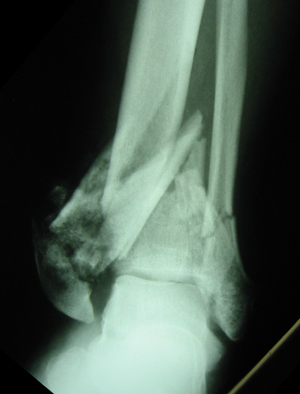

• Radiographs

• recommended views

• AP

• lateral

• mortise

• full-length tibia/fibula and foot x-rays performed for fracture extension

• findings

• 4 characterisic fragments

• medial malleolus

• anterior malleolus = chaput

• lateral malleolus = wagstaffe

• posterior malleolus = volkmann